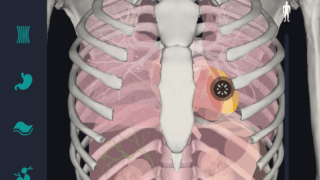

はじめに 本記事では、人体解剖学における専門的な部位の知識を始めに、効果的な勉強法についてご説明します。 人体解剖学では様々な器官や筋肉、骨の名称を覚えるだけではなく、体のどの位置に存在するのかまで覚えなければなりません。そのため、できるだ...